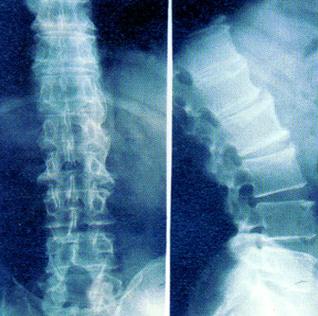

强直性脊柱炎有哪些好的治疗方法